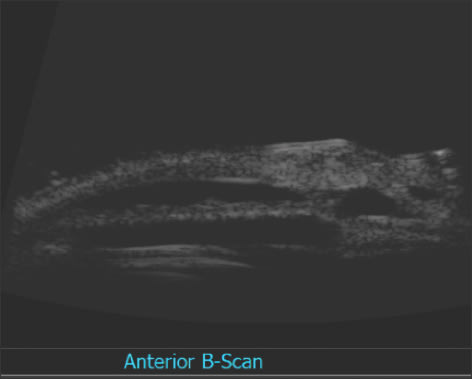

Next, Figure 4 below shows the “scleral lake” where the collagen wick has expanded. This does afford the ability to open the scleral flap or open the Descemet's window for pressure reduction.

Figure 4. This ultrasound image shows the scleral lake created by expansion of the collagen wick.